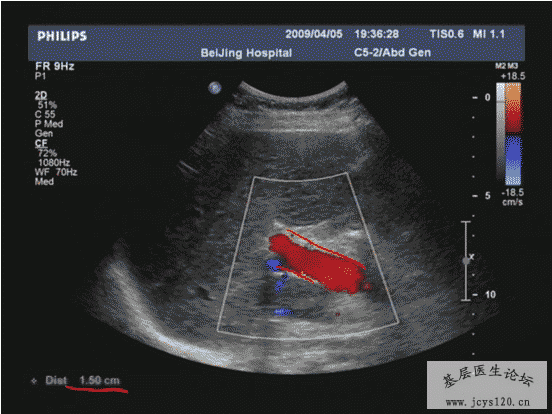

医学教育网讲义里面的精彩图片!